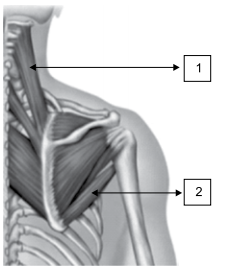

Assinale a alternativa que corretamente identifica os músculos dos membros superiores.